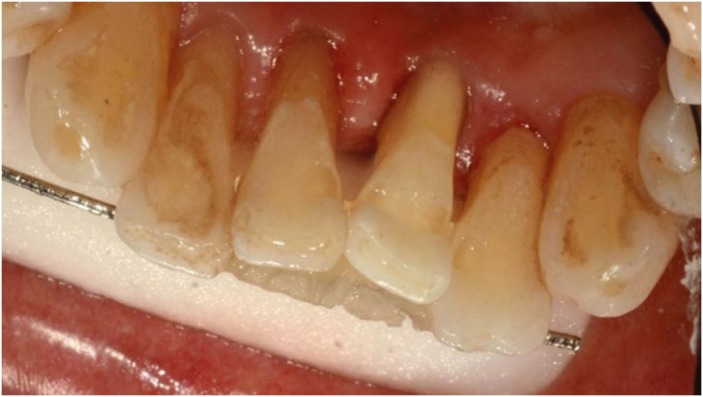

Figure 11

Lingual view after the abutment preparation was done.

rde-45-e8-g011.jpg

First, heavy calculus of the mandibular anterior teeth was removed before the procedure. After removal of the tooth, a direct FRC bridge was made in the same way as described above for case 1 (Figures 10, 11, 12).